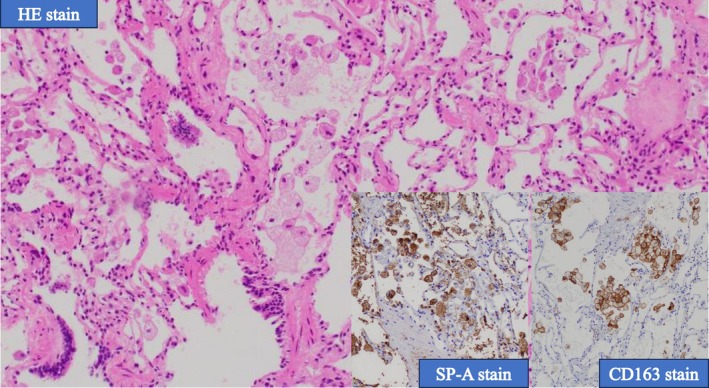

一位70岁的女性患者被诊断为IV期egfr突变型非小细胞肺癌,在接受化疗时经历了三种不同的外源性脂质肺炎。胸部CT一致显示毛玻璃混浊,呈疯狂铺路状,支气管镜检查证实脂质,cd163阳性泡沫巨噬细胞的存在。值得注意的是,每次发作都与不同的外源性暴露有关:鼻内施用凡士林,长时间使用煤油加热器,随后鼻内使用骏马润肤油。所有的发作都发生在右中叶,并在停止发作剂后得到解决。这是首例由多种不相关物质引起的单一患者复发性外源性脂质性肺炎的报道。该病例强调了放射学模式的诊断价值,细致的暴露史的重要性,以及在癌症治疗期间考虑新浸润患者的其他病因的必要性。

A 70-year-old female patient diagnosed with stage IV EGFR-mutant non-small-cell lung cancer experienced three distinct instances of exogenous lipoid pneumonia while undergoing chemotherapy. Chest CT consistently revealed ground-glass opacities with a crazy-paving pattern, and bronchoscopy confirmed the presence of lipid-laden, CD163-positive foamy macrophages. It is noteworthy that each episode was associated with a distinct exogenous exposure: intranasal administration of petroleum jelly, prolonged utilisation of a kerosene heater, and subsequently, intranasal application of Junma Moisturising Oil. The localisation of all episodes to the right middle lobe was noted, and resolution was attained with the cessation of the offending agent. This is the first reported case of recurrent exogenous lipoid pneumonia in a single patient caused by multiple unrelated substances. This case underscores the diagnostic value of radiologic patterns, the significance of meticulous exposure history, and the necessity of contemplating alternative aetiologies in patients with new infiltrates during cancer therapy.